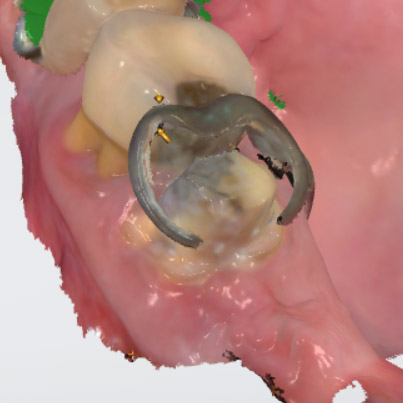

Hallmark Dental Laboratory Ltd. is a full-service dental lab that provides services to dentists across Canada. We specialize from dentures to crown & digital